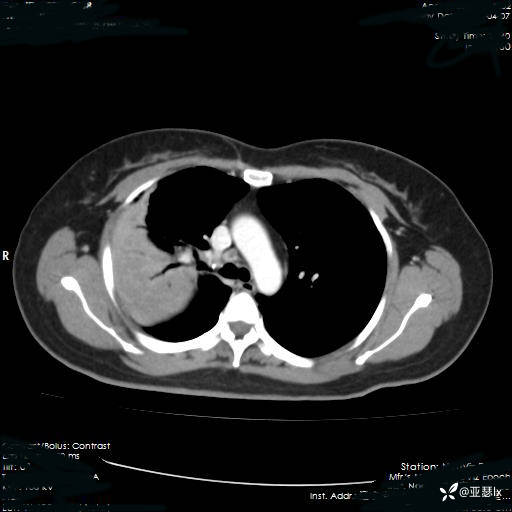

治疗后复查影像学(2023.04.07)

患者体温有所改善,但影像学未见明显变化,后续行肺穿刺活检检查。